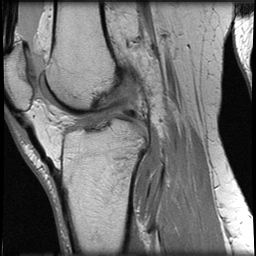

MRI of Torn ACL Ligament

MRI of Torn ACL Ligament

The ACL ligament can be seen between the femur and tibia bones of the leg. In the normal scan, it appears as a dark black filament intersecting the two bones. Note the apparent absence of the ligament on the abnormal MRI scan.